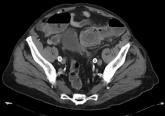

Large gallstone ileus

- Arif H. Kamal, MD

- Todd H. Baron, MD